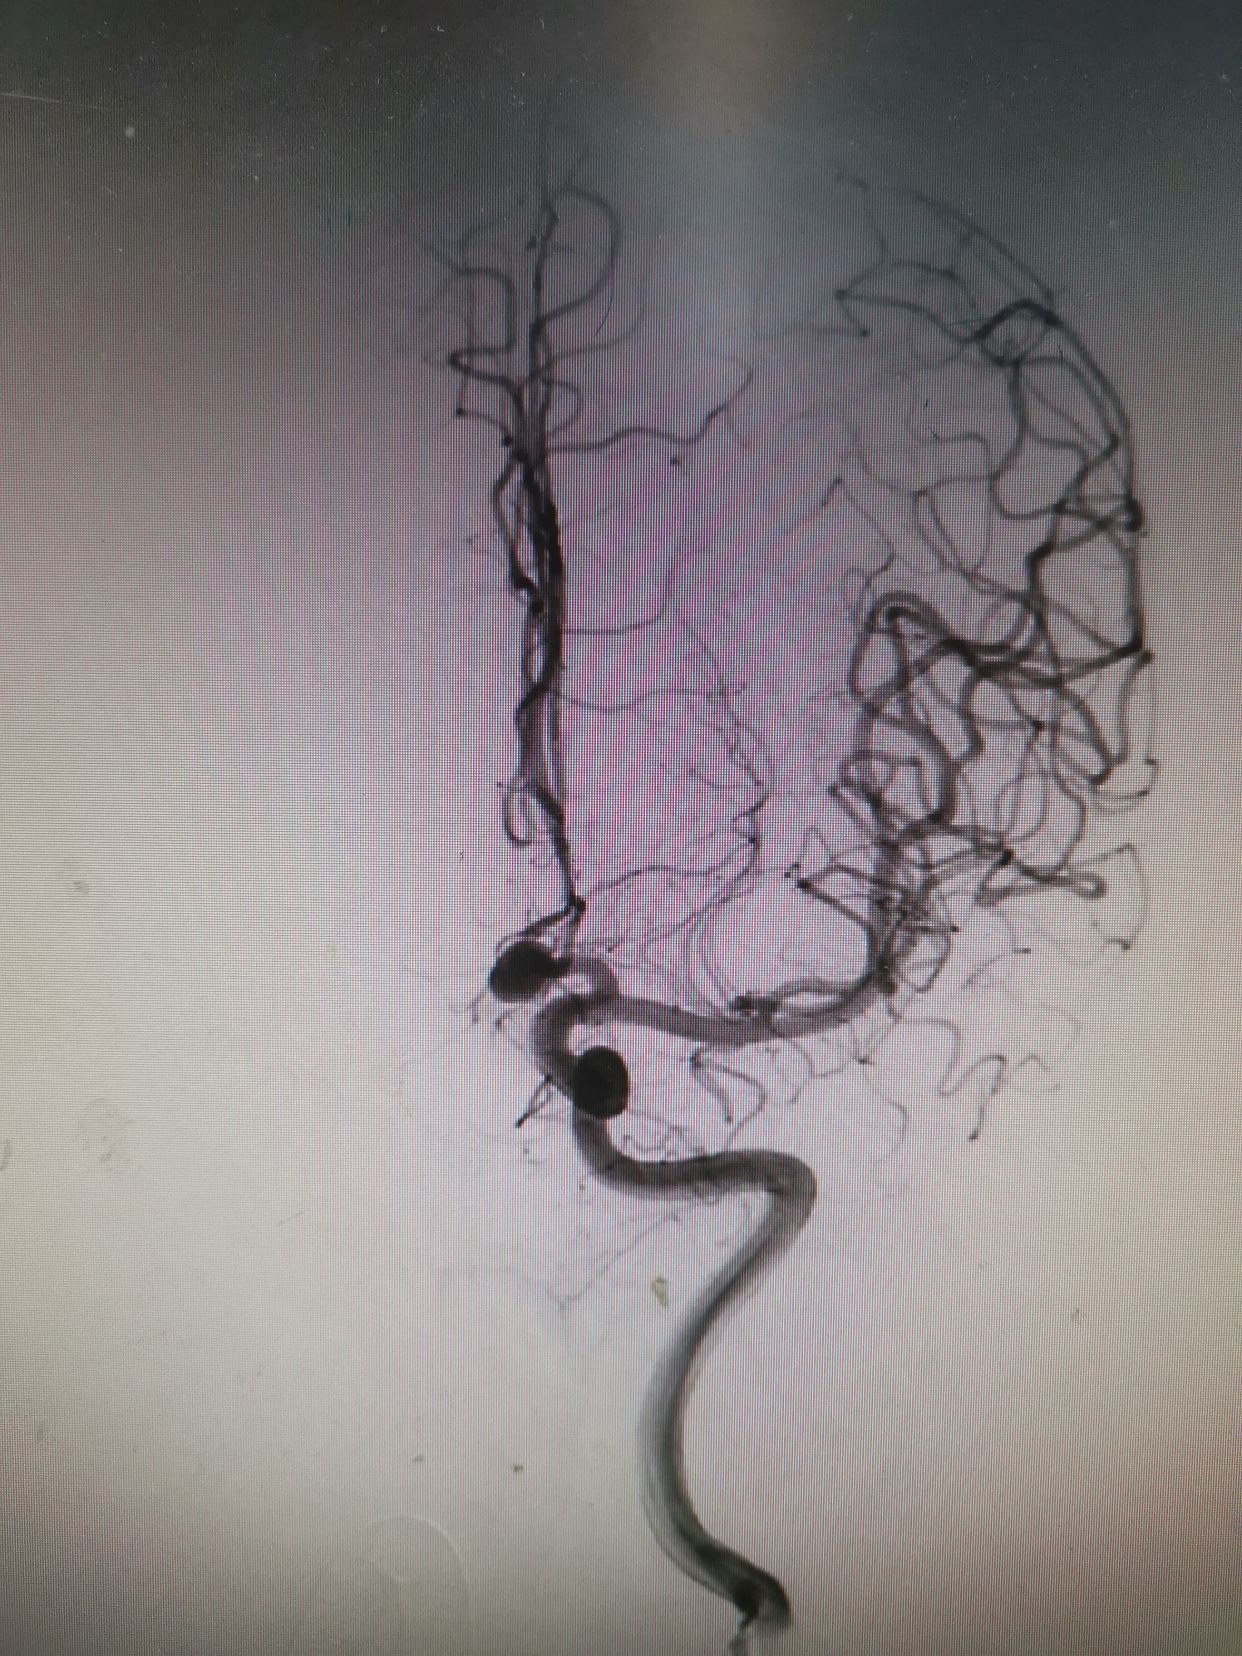

造影结束。患者全麻状态,观察患者瞳孔,右侧瞳孔散大,对光反射消失。立即行CT检查发现右额叶脑内血肿较前明显增加,脑内血肿形成。相关病情告知家属。拟立即快速行弹簧圈填塞术,术后直接入手术室行右侧开颅脑内血肿清楚术+去骨瓣减压术。

微导管到位后,填入Cosmos Complex 7mm/22cm

继续填入Complex 6mm/26cm

继续填入Complex 6mm/18cm

继续填入Complex 5mm/15cm

术后动脉瘤不显影,双侧大脑前显影。右侧略差。

介入填塞过程顺利,用时大约半小时,期间予20%甘露醇250ml静滴。后立即转入手术室行右侧开颅脑内血肿清除术。